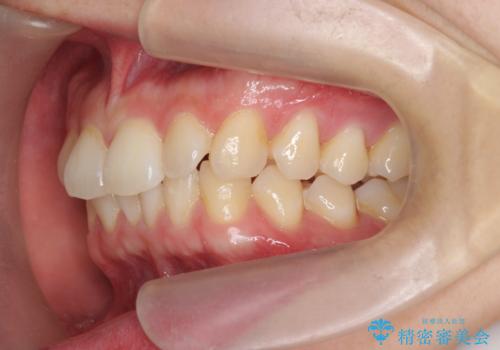

- 20代男性

- ワイヤー

- 10ヶ月

- 取り外しの必要なマウスピース矯正ではなくワイヤー矯正を希望され来院されました。

マウスピース矯正、ワイヤー矯正どちらの方法でも治療は可能ですが、ご要望の通りワイヤー矯正で歯の排列を行っていきます。